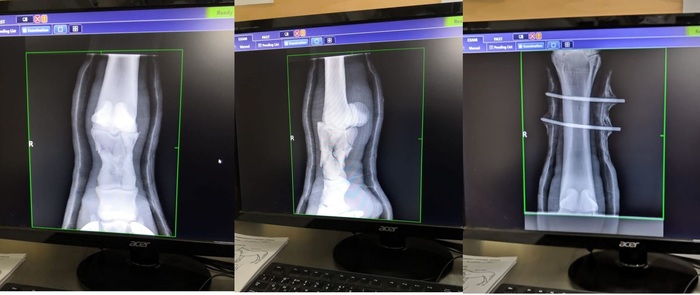

Рентгены ноги

перелом

Сейчас

Здоровая нога для сравнения

Одна из причин такого продолжительного времени срастания кости скорей всего кроется в проседании кости после снятия штифтов. Изначально, при переломе, кость очень сильно просела. На штифтах вытянулась, стали нарастать ткани. Когда штифты сняли ткани не выдержали и кость снова просела. (Их сняли раньше назначенного срока из-за подозрений на проблему с костью). Соответственно все ткани, образовавшиеся за это время, порвались. И с того момента, как кость приняла «окончательную позицию», весь процесс можно сказать пошёл заново...